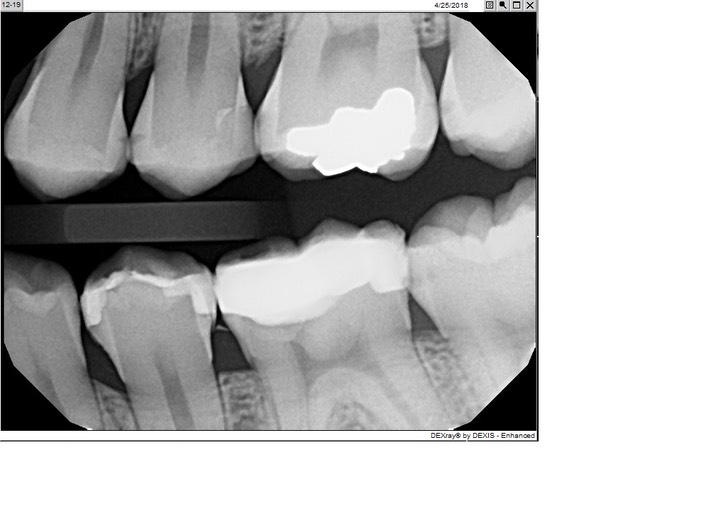

Kris Nip #19

JuliaTPost